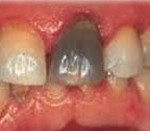

Выделяют несколько групп факторов, приводящих к возникновению некроза пульпы: химические, бактериальные, термические и механические. Химический некроз пульпы чаще всего возникает в результате применения агрессивных веществ на этапе лечения кариеса, например, спирта или фенола и тд Вещество проникает в пульпу зуба через дентинные канальцы, в результате чего происходит химический ожог тканей сосудисто-нервного пучка зуба, который заканчивается его некрозом. Химический некроз пульпы приводит к развитию воспалительных явлений в периодонтальной связке, окружающей зуб. Выявляется такой вид некроза случайно, при обнаружении на рентгенограмме изменений в периапикальных тканях зуба. Также внимание врача привлекает серый цвет твёрдых тканей. Такой зуб чаще всего ранее лечен по поводу среднего или глубокого кариеса.

Часто некроз пульпы развивается бессимптомно. Может обнаруживаться случайно при проведении рентгенологического исследования (ортопантомограммы, компьютерной томографии). В таком случае некроз часто сочетается с изменениями в периапикальных тканях зуба. В некоторых случаях пациент обращается к стоматологу с жалобами на изменение цвета зуба. При осмотре полости рта стоматолог обнаруживает зуб серого цвета. При вскрытии пульпарной камеры определяется гнилостный запах. Перкуссия таких зубов бывает положительной. Поверхностные слои пульпы грязно-серого цвета, не кровоточат. Зондирование корневой пульпы также может быть положительно.